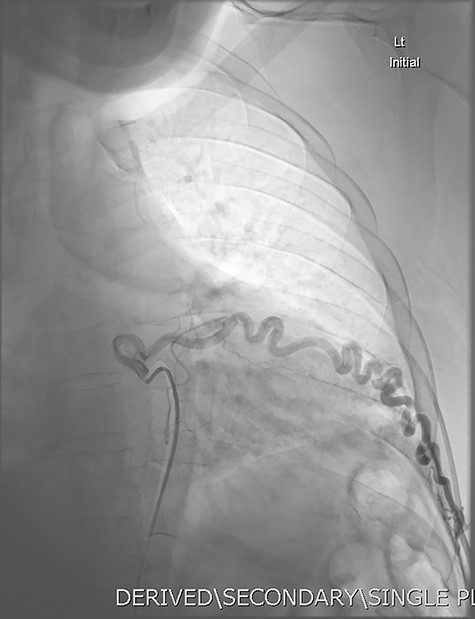

Aortic DSA using a pigtail catheter (green arrow), demonstrating extensive arterial collateralization between the left chest-wall intercostal arteries and the left lower lobe PAVM.

Given the findings, he was referred to Interventional Radiology for a formal digital subtraction angiogram with view of transcatheter embolization. Under local anaesthetic and sedation, a 5-french sheath was placed in the left common femoral artery. Using a 5-french pigtail catheter, aortic angiography was undertaken, confirming the CTPA findings and demonstrating predominant supply of the vascular malformation via the left intercostal arteries and the left inferior phrenic artery (Fig. 4)—draining into the left inferior pulmonary artery and vein. Superselective catheterization of the left intercostal arteries (Fig. 5) and the left inferior phrenic artery (Fig. 6) are shown. Unfortunately, due to the malformation’s volume and complexity, embolization was abandoned. He was subsequently referred to Cardiothoracic Surgery, currently awaiting consideration and workup for ligation and resection via video-assisted thoracoscopy, and potentially thoracotomy.